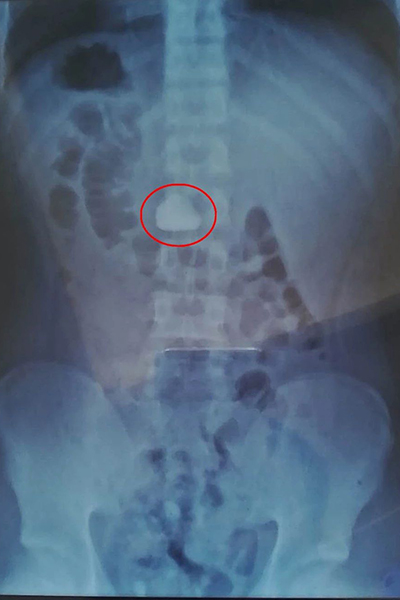

紅圈內(nèi)為X光透視下胃內(nèi)的石頭

▲紅圈內(nèi)為X光透視下胃內(nèi)的石頭

由于情況特殊,我院消化內(nèi)科團隊立刻為小李進行了查腹部立位片,結(jié)果提示:石頭均已進入胃中。在這種情況下有兩種治療方案,第一保守治療:通過服用大量含粗纖維素的食物(如韭菜),幫助胃腸蠕動通過排便排出。第二種就是通過電子胃鏡將石頭取出來。

第二天小李排便后復(fù)查腹部立位片提示:仍有一塊較大石頭留在胃中未能排除。且小李出現(xiàn)了持續(xù)的惡心、不適等癥狀。考慮與石頭較大胃部蠕動時石頭刺激胃粘膜有關(guān),如果不能及時取出,長期刺激可造成胃粘膜糜爛、出血、穿孔等風(fēng)險。綜合考慮并與患者溝通后我院消化內(nèi)科團隊給予內(nèi)鏡取石。

我院消化內(nèi)科曾多次內(nèi)鏡下取出異物,但內(nèi)鏡下取石還是第一次,且通過兩次X線對比,粗略估計石頭直徑大于3cm,大于食管平均直徑,且石頭形態(tài)不規(guī)則,取石風(fēng)險極大,稍有不慎就容易劃傷食管或造成食管穿孔。